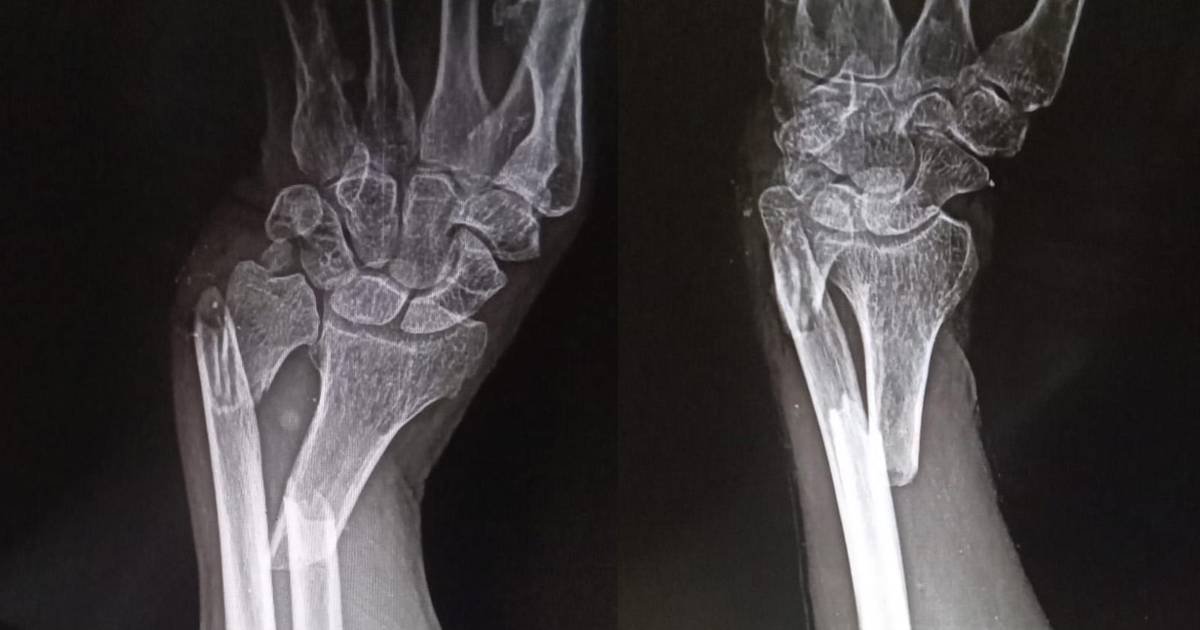

Estas son las radiografías del cacique

Existe impotencia en comunidades originarias de San José de Chiquitos por la brutal agresión de la que fue víctima Ricardo Peña, un cacique de 70 años al que dos hombres golpearon hasta provocarle fracturas en ambos brazos. Sospechan que los responsables son parte de un grupo de avasalladores.

Al retornar a su hogar, fue seguido por dos jóvenes, quienes lo atacaron por detrás, dejándolo aturdido por el impacto y procedieron a agredirlo con tanta violencia que le rompieron sus muñecas y lo dejaron ensangrentado a un lado del camino.